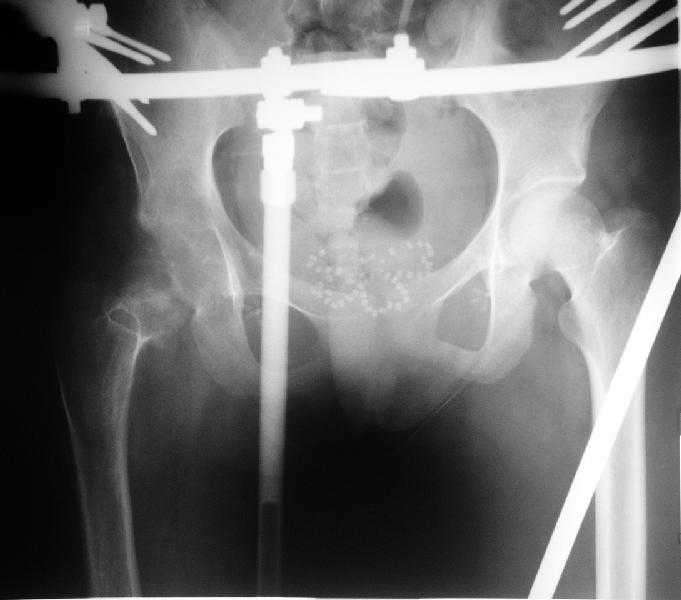

Больная 18 лет. Травма 12.08.2007. Лечилась в одном из городов Свердловской области.

15.08.2007 в ЦРБ сделан открытый остеосинтез правого бедра интрамедуллярным стержнем, после чего была наложена гипсовая кокситная повязка и пациентка лечилась амбулаторно в течение 1,5 месяцев. На контрольном Rn исследовании в марте 2008 диагностирован подвздошный вывих правого бедра. <br><br>

Поступила к нам в отделение. В отделении первым этапом был наложен аппарат внешней фиксации для низведения  бедра. 30.09.08 интрамедуллярный стержень удален. Вторым этапом планируется эндопротезирование. В настоящее время у больной имеется контрактура коленного сустава, с амплитудой движений в пределах 30 градусов., и выраженный остеопороз вертлужной впадины и проксимального отдела бедра. Больныя пердвигается самостоятельно с опорой на здоровую ногу и костыли. <br><br>